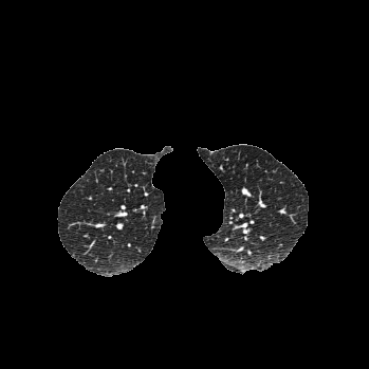

COPDGene / Dirlab lung CT. We follow the data selection and preprocessing of [23]. We train on 999 inhale/exhale pairs from COPDGene [18], masked with lung segmentations, clipped to [-1000, 0] Hounsfield units, and scaled to (0, 1). We evaluate landmark error (MTRE) on the ten inhale/exhale pairs of the Dirlab challenge dataset [4]333https://tinyurl.com/msk56ss5.

| Moving Image | Warped Image | Fixed Image | Moving Image | Warped Image | Fixed Image |